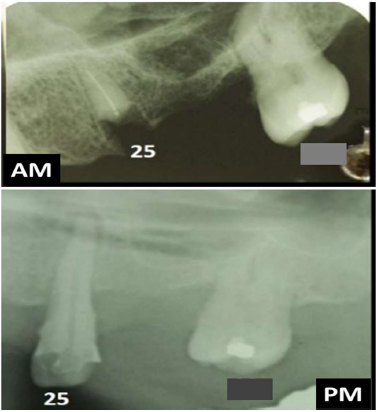

As radiografias odontológicas possuem grande importância para a identificação humana, pois podem exibir particularidades anatômicas, terapêuticas e patológicas específicas de um indivíduo, cujo corpo não pode ser identificado pelas impressões digitais, como nos casos de corpos carbonizados, putrefeitos e em decomposição avançada. Para subsidiar uma identificação utilizando-se radiografias odontológicas torna-se importante reproduzir no exame pós-morte (PM) as mesmas estruturas evidenciadas no exame produzido antes da morte (AM). Sobre os aspectos técnicos e periciais inerentes a uma identificação radiológica odontológica, analise as afirmativas a seguir, tendo como base uma adaptação realizada no confronto radiográfico AM e PM do trabalho publicado por Pereira e colaboradores (2021), sabendo-se que o lapso temporal entre as radiografias AM e PM é de cerca de 4 anos.

I. Neste confronto radiográfico AM x PM, há 5 similaridades considerando os dentes presentes e ausentes.

II. Uma das similaridades anatômicas é a ausência do dente 28 (perda antiga) e uma similaridade terapêutica é a presença de material restaurador no dente 27.

III. Por haver pelo menos 6 similaridades e uma discrepância explicável no dente 25, a identificação pode ser positiva.

IV. Mesmo havendo pelo menos 6 similaridades, a presença de uma discrepância inexplicável no dente 25 remete a uma exclusão.

Fonte: imagem adaptada do artigo científico de autoria de Pereira e colaboradores (2021), publicado na Revista Brasileira de Odontologia Legal, v. 3, n. 8, p.95-102.